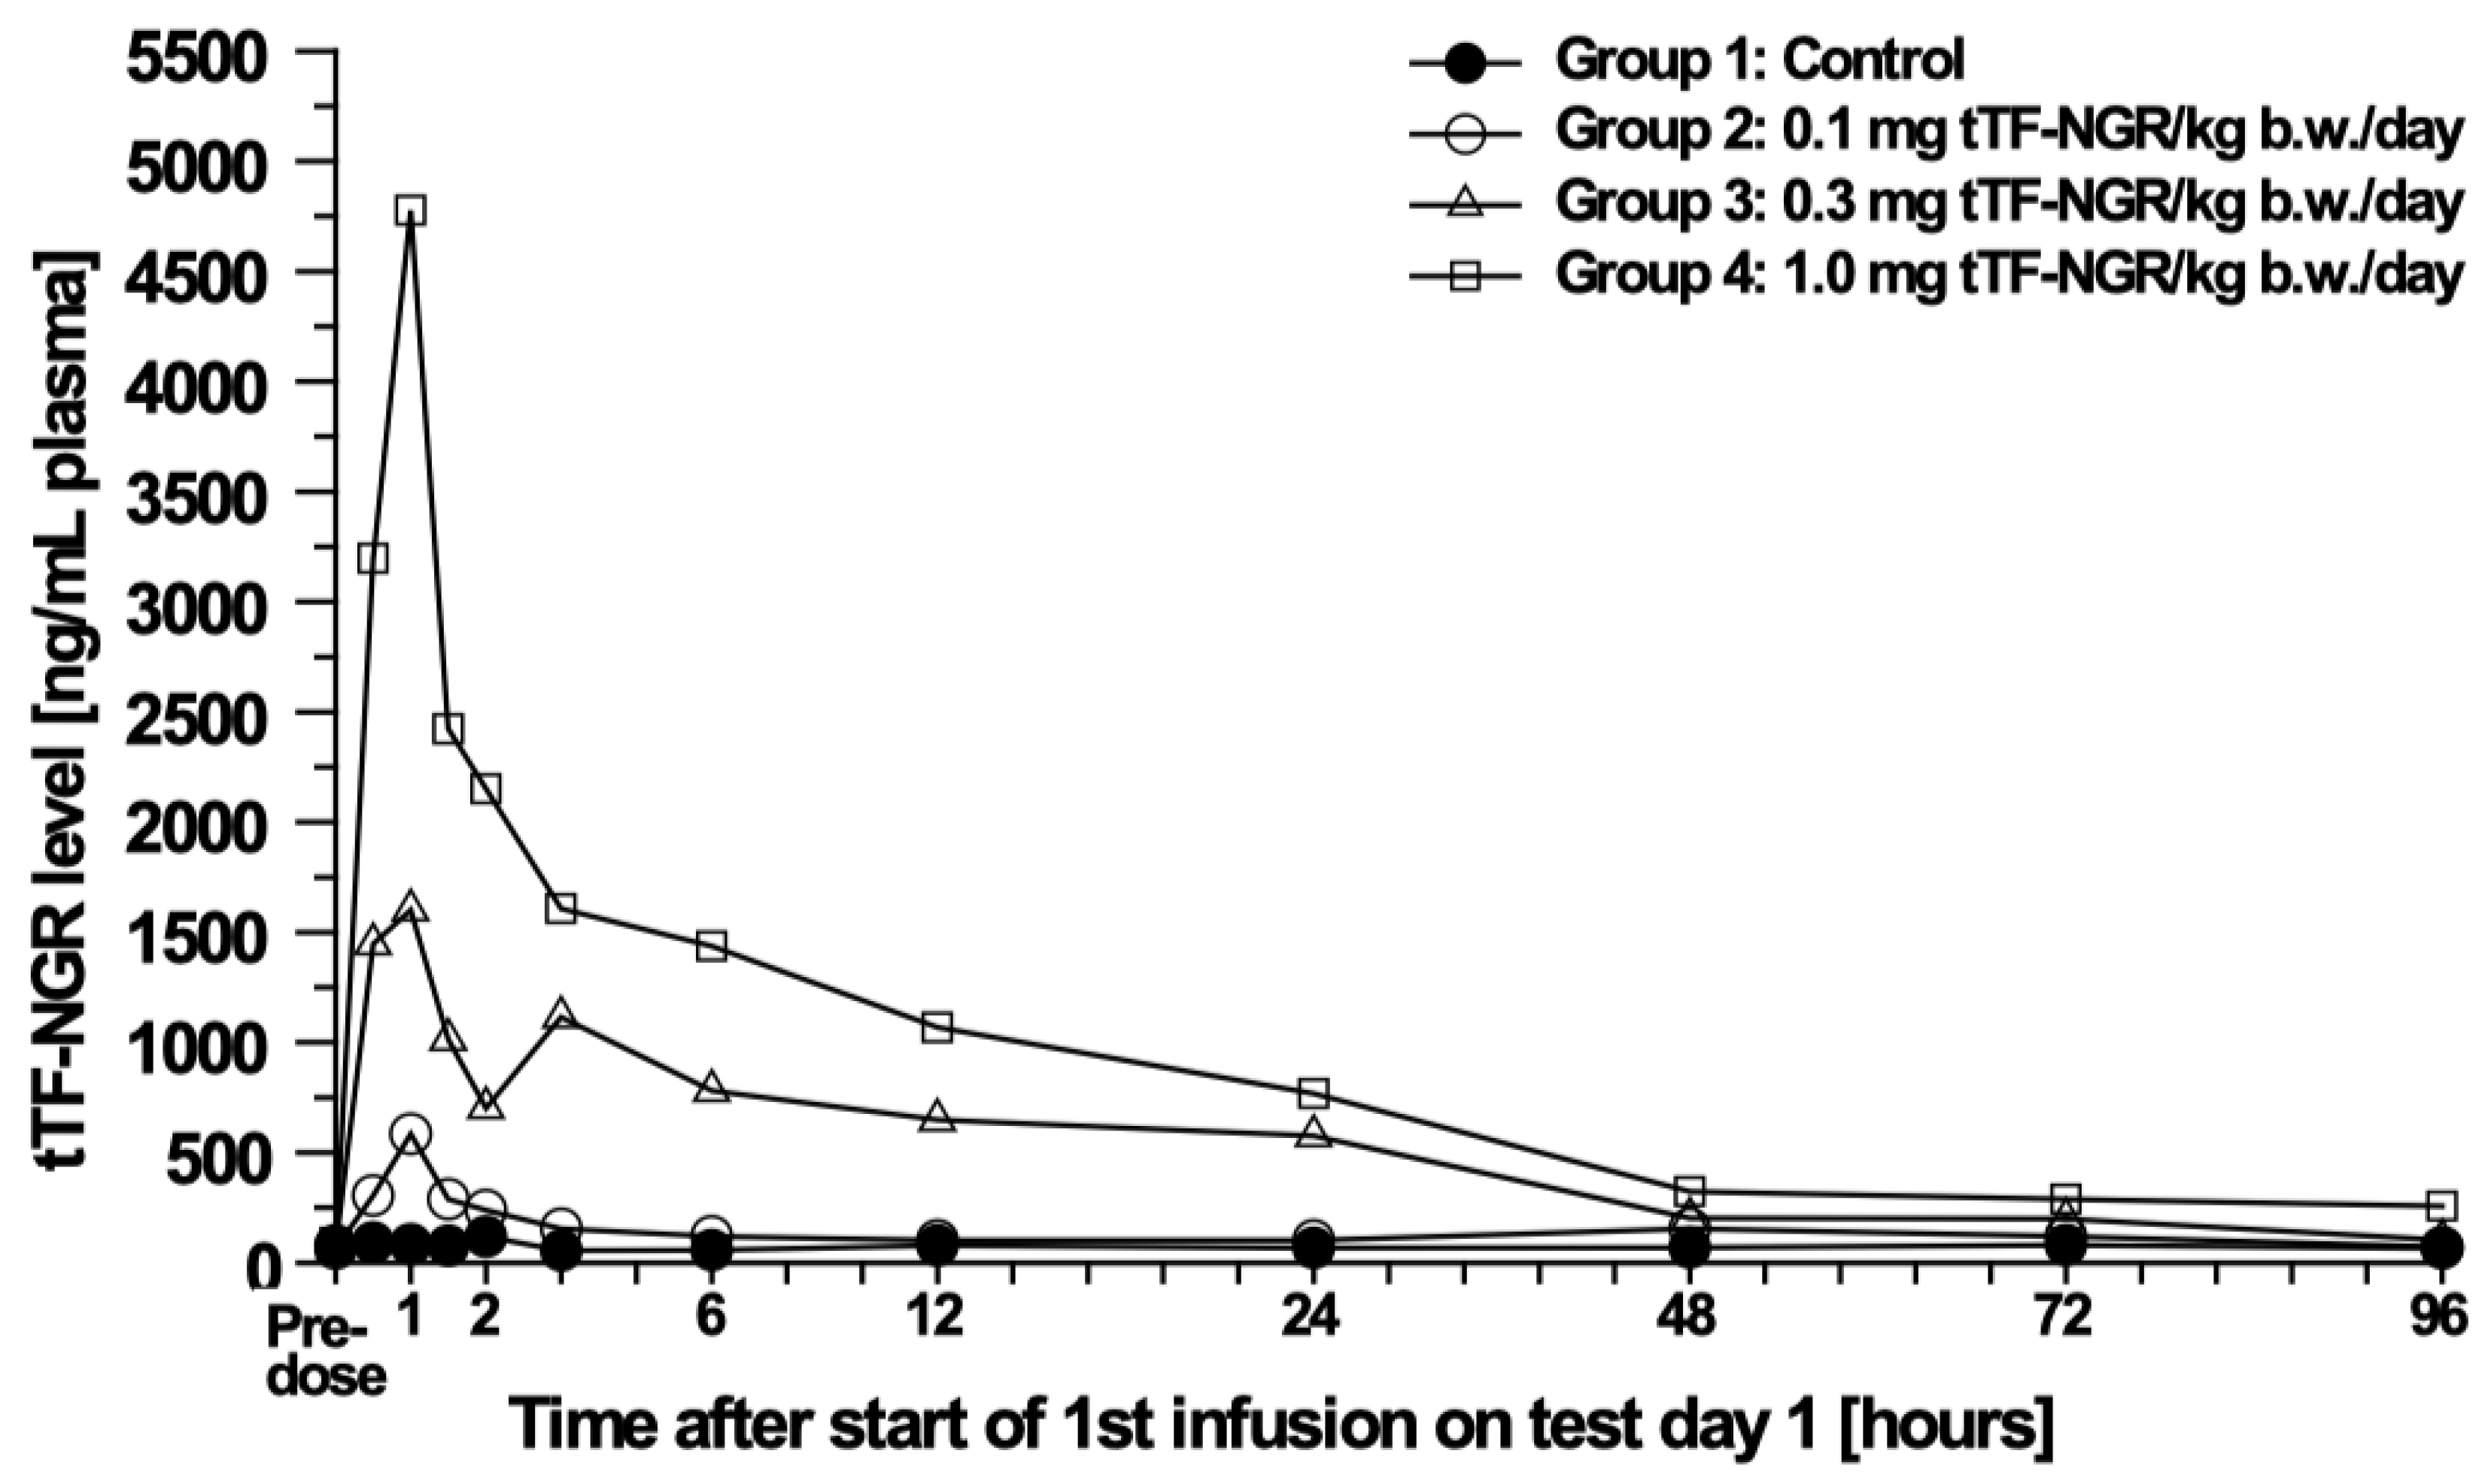

3.3. Pharmacokinetic (PK) and Toxicokinetic Studies in Beagle Dogs

4.3.3. Pharmacokinetics (PK)

4.4. Central Statement and Consequences to Be Discussed